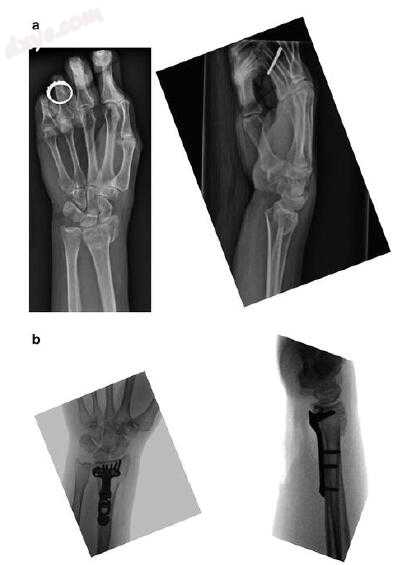

图19.1自发性破裂。 (a)受伤时的初始X光片显示粉碎的背侧移位桡骨远端骨折。 (b)术后透视薄膜显示用背侧突出的螺钉充分减少

一名54岁的右手优势女子参与了机动车事故。 她接受了急诊科的闭合复位评估。 离开急诊室后,她注意到拇指和食指在向手外科医生报告时出现严重的麻木和刺痛感。 鉴于显著的背部粉碎以及正中神经症状,在一周内进行手术固定和腕管释放。 一个月后,她在手背上感到疼痛,无法伸展拇指指间关节。 在第三或第四隔室中手术时没有显示突出的螺钉(图19.1)。